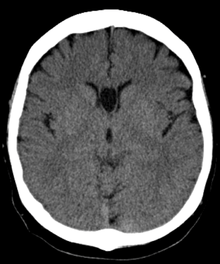

The cave of septum pellucidum (CSP) describes a septum pellucidum that has a separation between its two leaflets (septal laminae). This cavity contains cerebrospinal fluid (CSF) that filters from the ventricles through the septal laminae.[1]

The cave of septum pellucidum is bounded anteriorly by the genu of the corpus callosum; superiorly by the body of the corpus callosum; posteriorly by the anterior limb and pillars of the fornix; inferiorly by the anterior commissure and the rostrum of the corpus callosum; and laterally by the leaflets of the septum pellucidum.[2]

The most common type of CSP is noncommunicating, that is, it does not connect to the brain's ventricular system. Because of this lack of communication, the erstwhile term for CSP, the "fifth ventricle," is not anatomically correct and its use has fallen out of favor in recent years.